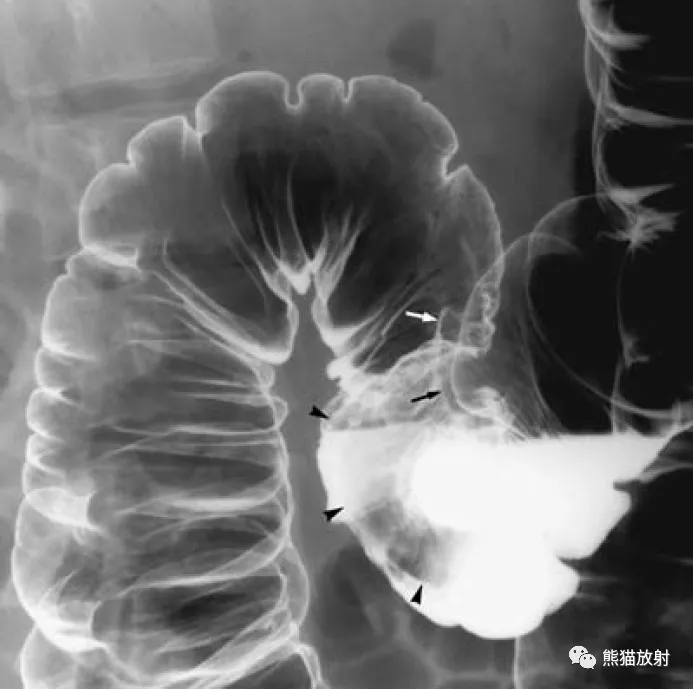

(图) 大肠的x线像(前后位)-人体解剖组织学-医学

8 盲肠,9 乙状结肠,10 阑尾,11 直肠 十一,直肠 图22 直肠解剖示意图